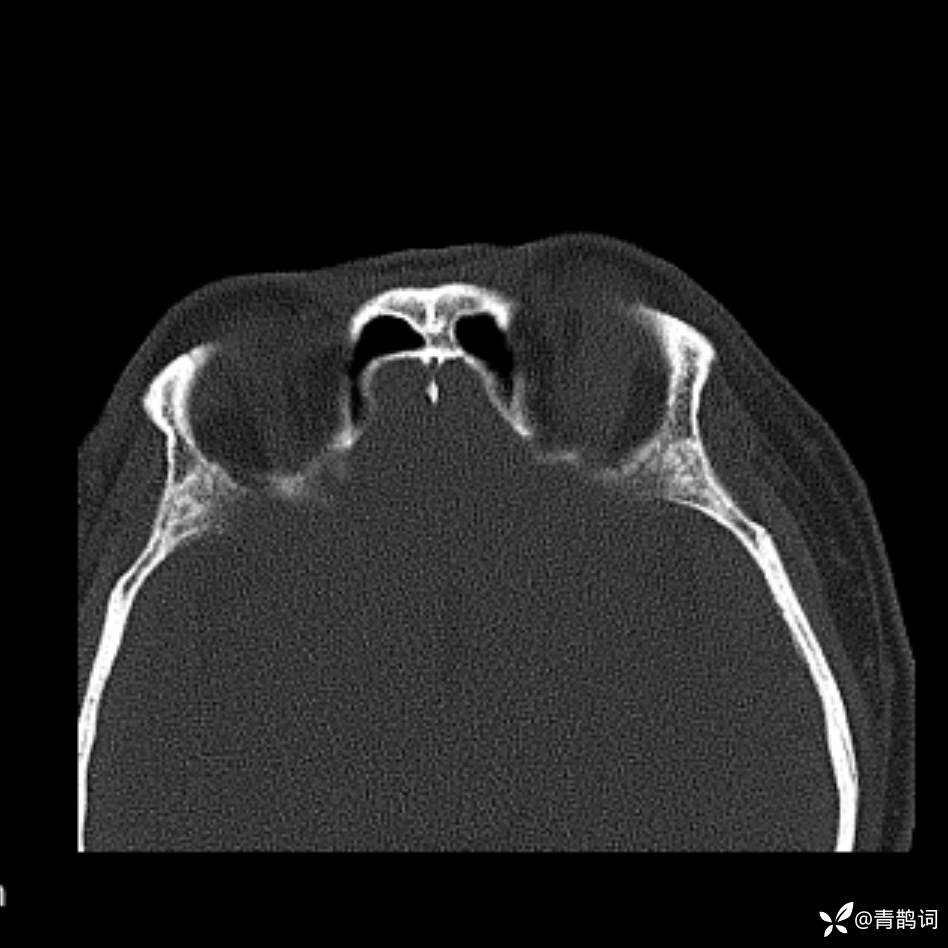

患者年龄:30岁。

患者性别:男。

简要病史:左颜面部肿胀2年,反复咳嗽咳痰,逐渐加重。

结合病史及影像学表现,期待评论区各位老师各抒己见~